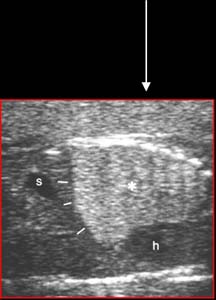

MAKP - microkystique